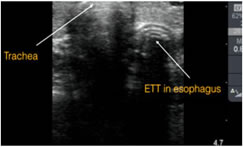

Tracheal intubation if only one air-mucosal (A-M) interface with reverberation artifact and posterior shadowing was observed and Esophageal intubation if two A-M interfaces posterior shadowing were noted, which is called a double tract sign.

Figure 2: